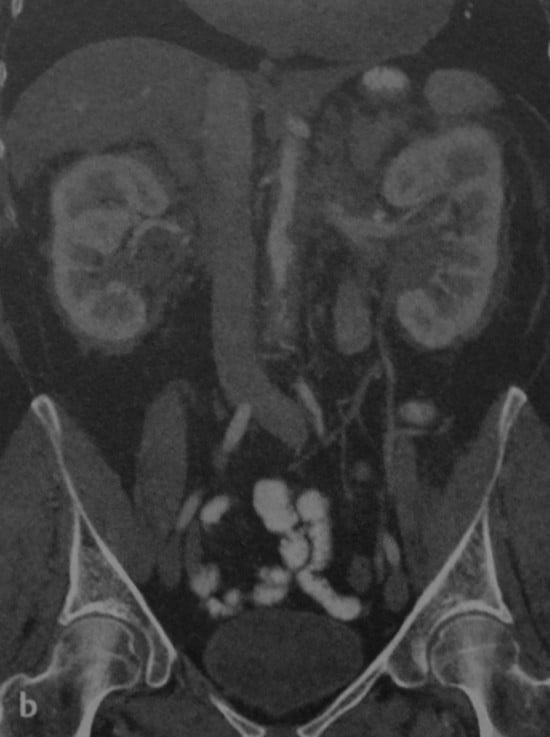

КТ ретроперитонеального фиброза: Изображения и диагностика